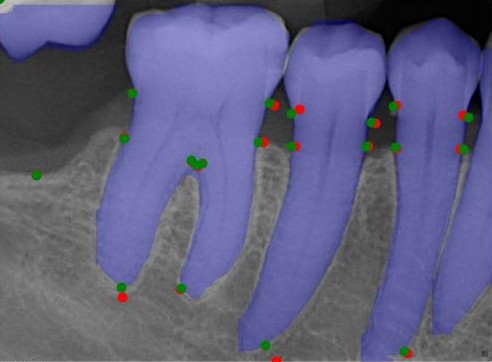

We conducted comprehensive annotation of the collected radiographs, divided into four steps. These include annotating Bone Level Keypoints (BLK) for each tooth, identifying the Teeth Bounding Box (TBB) with tooth orientation, annotating ARR keypoints, and widened PLS bounding boxes. Figure 1 provides visual examples of the annotations.

Refer to caption

Figure 1: Three images containing example annotations of the collected keypoints and rotating bounding boxes.